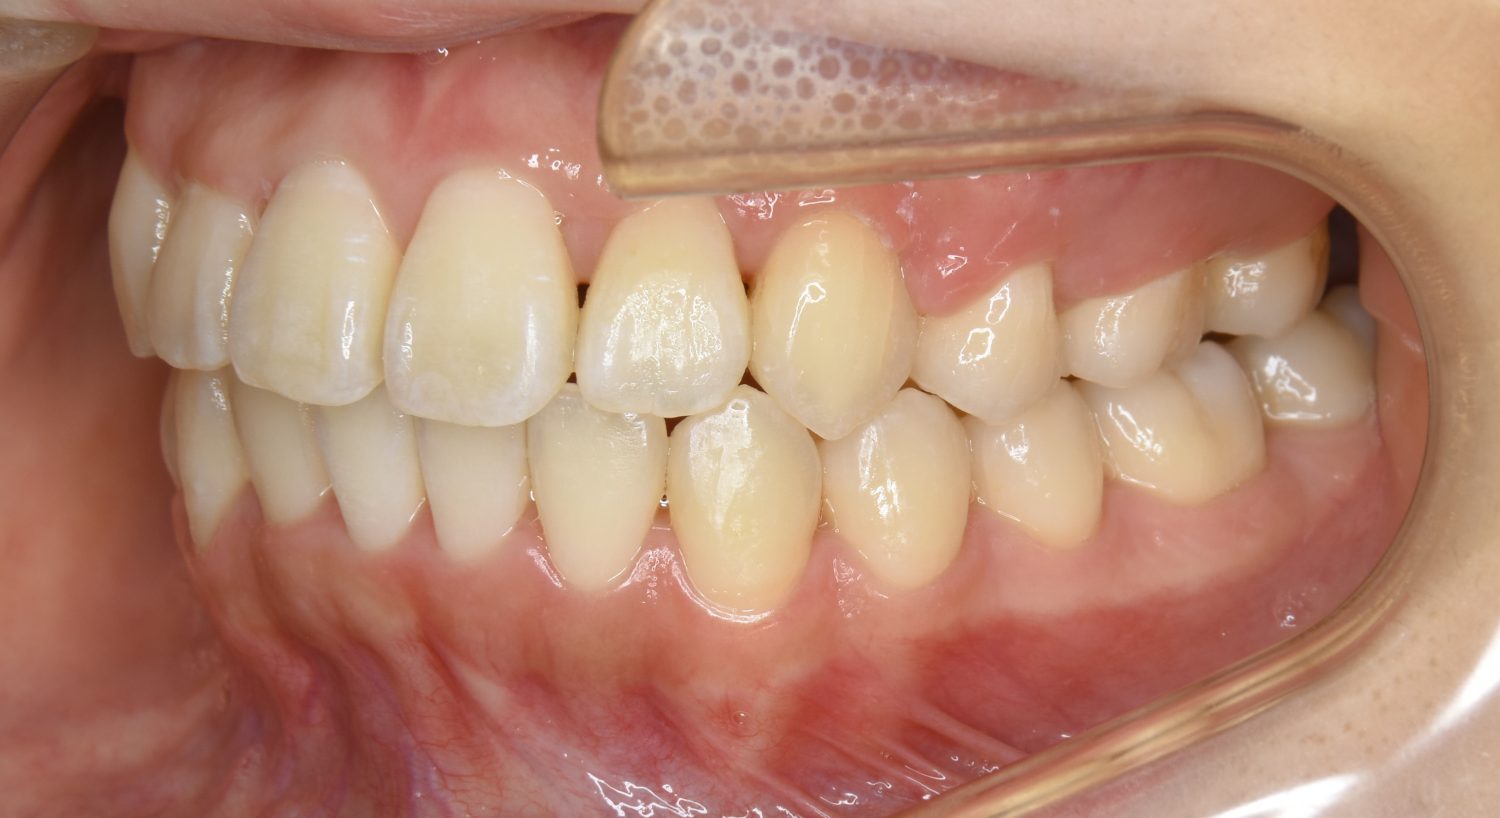

上顎前突の症例紹介①

Before

After

主訴

上の歯が出ている。歯並び全体が気になる。

治療内容

上顎両側第一小臼歯を抜歯し、上下ラビアルブラケット(唇側装置)に矯正用アンカースクリューを併用し治療を行いました。

上顎前歯の前突により口元の突出が認められました。上の左右の第一小臼歯を抜歯し上顎前歯を後退させることで口元の突出感は改善し、咬合も良好な状態となりました。